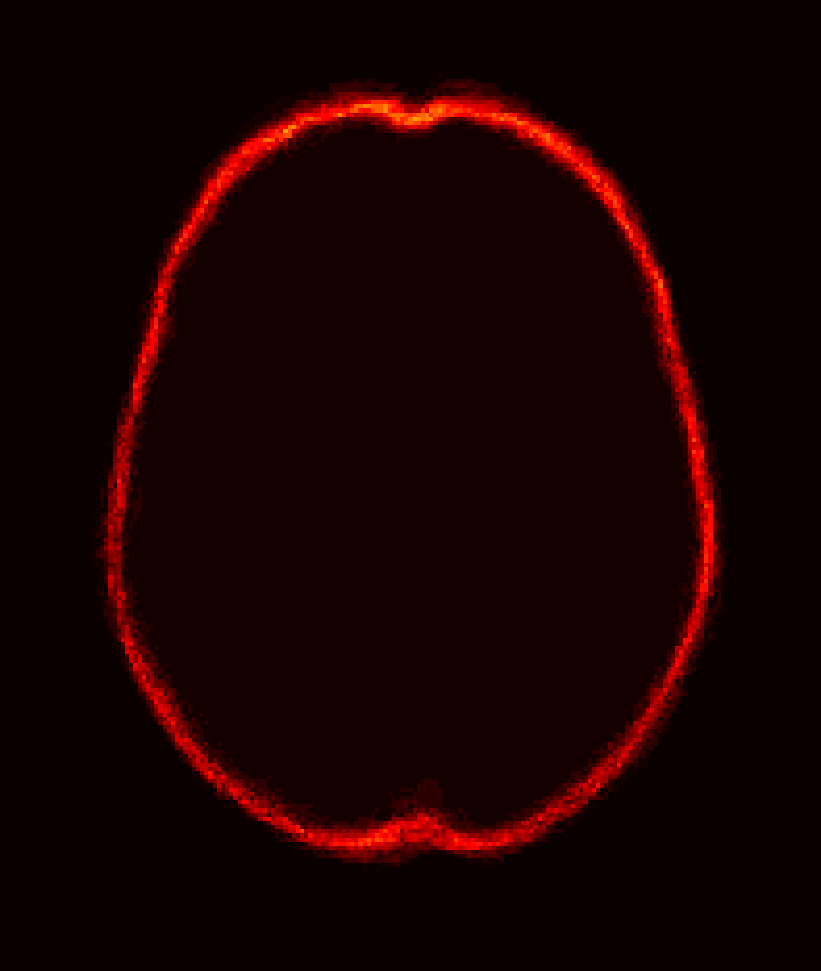

Fig. 1 shows example images from each dataset to illustrate image variability. IBSR and LPBA40 contain images from normal subjects and include large portions of the neck; BRATS has very low out-of-plane resolution; and the TBI dataset contains large pathologies and abnormal skulls.

Refer to caption

Figure 1: Illustration of image appearance variability on a selection of images from each (evaluation) database. From top to bottom: IBSR, LPBA40, BRATS and TBI.